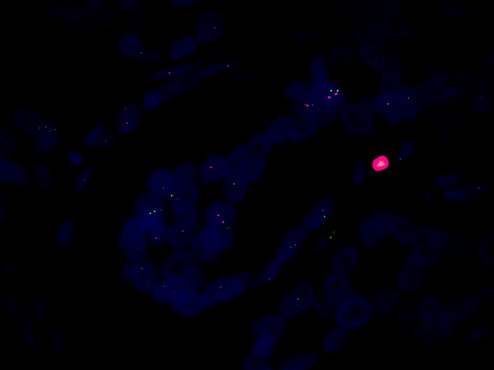

HER-2 是一種蛋白質(zhì),通常在乳腺癌和其他癌癥中過(guò)度表達(dá)。通過(guò)檢測(cè) HER-2 的表達(dá)水平,可以早期診斷乳腺癌,并幫助醫(yī)生制定合適的治療方案。

FISH熒光原位雜交是一種先進(jìn)的顯微鏡技術(shù),可以用于檢測(cè) HER-2 的表達(dá)水平。在癌癥早篩中,熒光顯微鏡MF43-N可以用于對(duì)熒光染色的細(xì)胞進(jìn)行觀察,然后通過(guò)觀察細(xì)胞中不同信號(hào)點(diǎn)的數(shù)量和分布來(lái)檢測(cè) HER-2 的表達(dá)水平。這種技術(shù)可以有效地檢測(cè)出 HER-2 過(guò)度表達(dá)的細(xì)胞,為癌癥的早期診斷提供重要依據(jù)。

總結(jié)起來(lái),熒光顯微鏡MF43-N結(jié)合FISH熒光原位雜交技術(shù)觀察 HER-2,是癌癥早篩中的有效技術(shù)。通過(guò)使用這種技術(shù),可以有效地檢測(cè)出癌癥的早期跡象,從而提高患者的生存率。